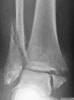

X-ray : 외과 골절(Lateral malleolar fracture)